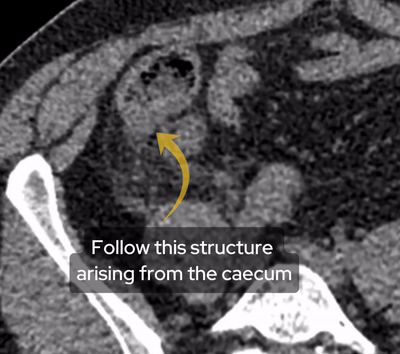

A male in his 50s presents to the ED with back and abdominal pain as well as a fever. He has a post contrast CT of his abdomen and pelvis in a portovenous phase. What is the most likely diagnosis?

With any abdominal or back pain, remember to assess the psoas major muscles which originate from the T12 to L5 vertebrae and transverse processes . These then join up with muscle fibres from the iliacus muscle and insert into the lesser trochanter of the femur.

The psoas muscles originate from the vertebral bodies of T12-L4, these intervertebral discs and the transverse processes of L1-L5. It then inserts into the lesser trochanter of the femur as the iliopsoas tendon.